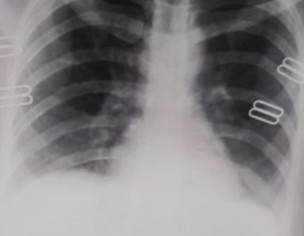

My brother is covid positive. He is diabetic too. He is having sore throat and body ache now. The attached photo is his chest X-ray. Can you please tell what’s his state now.

Chest d rat show inflamation in lungs consult online for detailed assessment